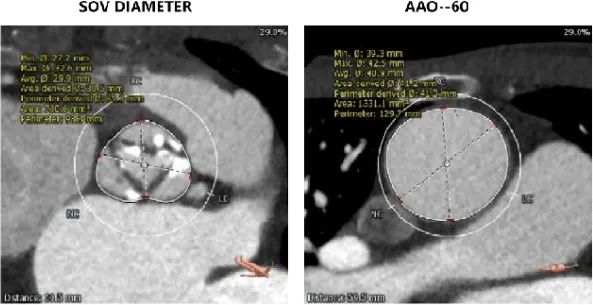

主动脉根部评估:

左冠开口高度12.0mm,右冠开口高度17.8mm,左冠高度较低,根据瓦氏窦内径和瓣叶长度综合判断,左冠存在较高堵塞风险;左室腔增大,心室壁未见明显增厚。

在术前评估阶段,首先通过心电图及超声探查,对患者心力储备、心脏电生理状况有了一个基本的把握,明确了患者自身的完全左束支传导阻滞,以及低 LVEF 情况。之后的 CTA 评估,通过瓣环上平面测量,提示了瓣叶较大冗长,上缘延展于 STJ 平面以上。于术前明确了冠脉极高闭塞风险,指示术中球囊预扩时,除常规 Balloon sizing 再次确认瓣膜型号外,还应当着重观察左冠灌注情况。

因此,在手术策略的制定上,我团队根据患者瓣环平均径及周长数据(24.0mm/79.1mm),基于高钙化患者 down size 方案及降低冠脉封堵风险考虑,选择了 26mm TaurusElite 瓣膜进行植入。术中采用 22mm TaurusAtlas 球囊预扩后,显示轻微腰征,造影无渗漏,左冠开口显影不明显,验证了术前判断。遂预埋冠脉支架,行烟囱支架置入术。